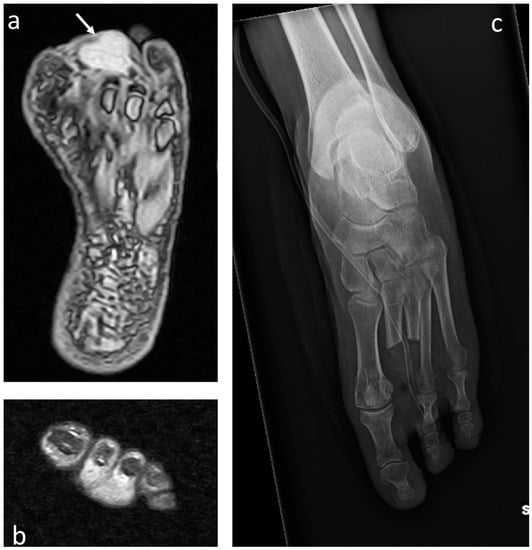

3.1. Osteosarcoma

3.2. Chondrosarcoma

3.3. Ewing Sarcoma